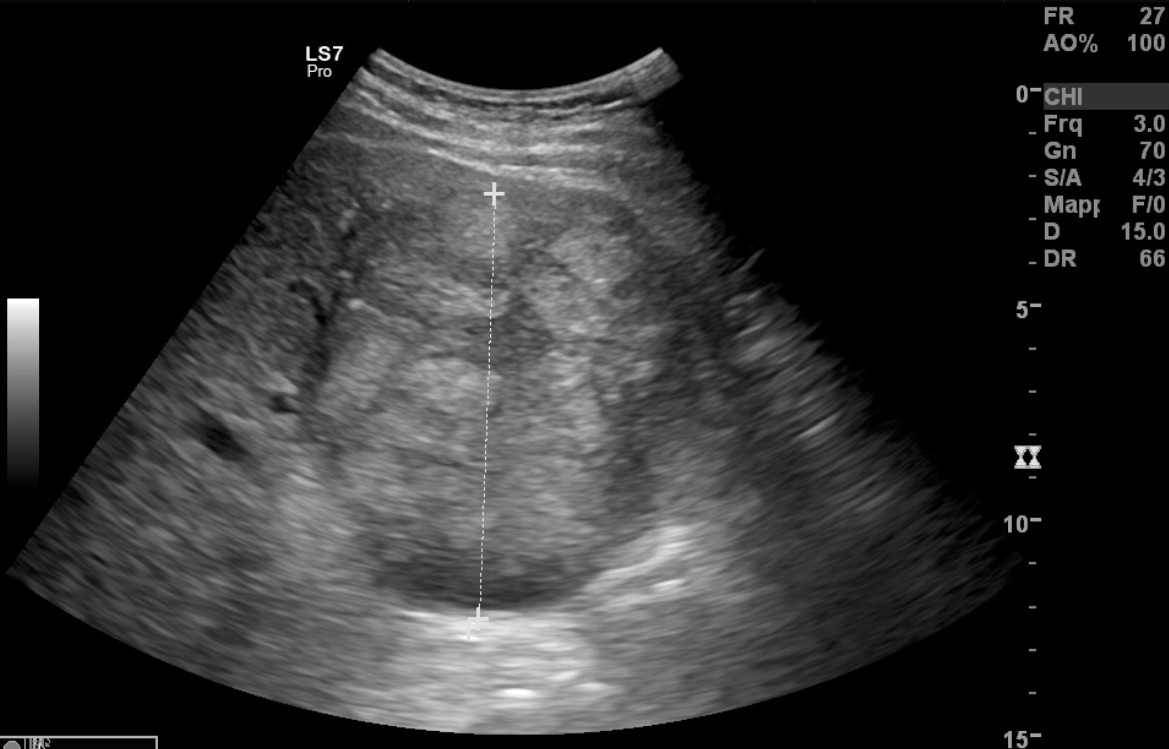

Ad oggi sono state identificate con l’ecografia addominale prevista dal protocollo, 9 neoplasie del parenchima epatico: 5 angiosarcomi (Fig. 1-4) (di cui 2 viventi) e 4 epatocarcinomi (Fig. 5-7) (di cui 1 vivente), successivamente sottoposte a studio TC e tutte confermate dalla diagnosi istologica.

Fig.2. Caso 1 di angiosarcoma epatico

Fig.3. Caso 2 di angiosarcoma epatico